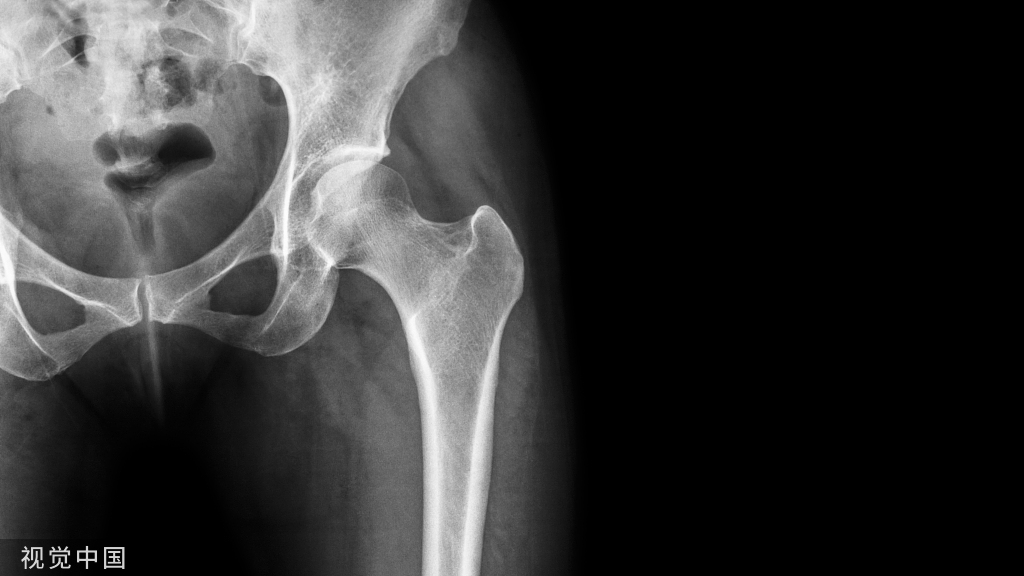

糖尿病药物对骨标志物的影响

越来越多的研究发现,不同类型的降糖药物对骨折风险有差异,其机制可能与对骨转换标记物的影响有关。表2总结了临床常见的几种降糖药物对骨折相关不同参数的影响。